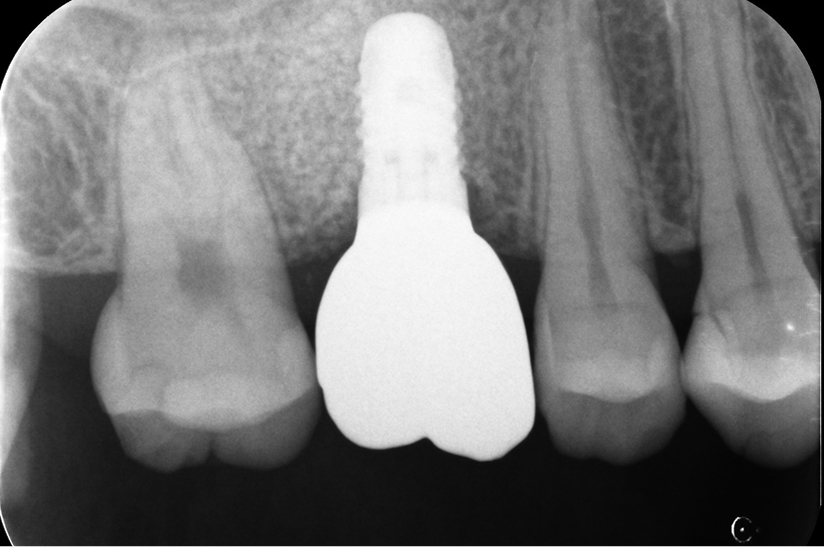

臼歯部(奥歯)単独インプラントで

他の天然歯を守った症例

タップで写真の拡大ができます。

Before

After

主訴

噛むと痛い、歯茎が腫れてきた

治療内容

抜歯即時インプラント埋入、リッジプリザベーション(顎堤温存術)

治療期間

6〜8ヶ月

治療費用

649,000

治療の

リスク

オッセオインテグレーションが得られなかった場合、撤去、再度埋入の可能性